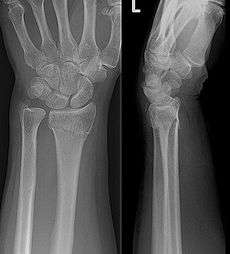

Diagnosis may be evident clinically when the distal radius is deformed but should be confirmed by X-ray. The differential diagnosis includes scaphoid fractures and wrist dislocations, which can also co-exist with a distal radius fracture. Occasionally, fractures may not be seen on X-rays immediately after the injury. Delayed X-rays, X-ray computed tomography (CT scan), or Magnetic resonance imaging (MRI) will confirm the diagnosis.

Medical imaging

X-ray of the affected wrist is required if a fracture is suspected. CT scan is often performed to investigate the articular anatomy of the fracture, especially if surgery is considered. Investigation of a potential distal radial fracture includes assessment of the angle of the joint surface on lateral X-ray, the loss of length of the radius from the collapse of the fracture, and congruency of the distal radioulnar joint. Displacement of the articular surface is the most important factor affecting prognosis and treatment.

Lateral articular angle

The lateral articular angle is the angle on an x-ray film between the axis of the radius and the articular cup. Normally, the angle is tilted toward the thumb (volar/ventral tilt) by 11°. The most common fracture pattern usually demonstrates malalignment of this angle and collapse in a dorsal direction. Alignment up to 0° is still considered to be functional, and does not require any intervention. However, tilt away from the thumb (dorsal tilt) beyond this point (>11° deviation) begins to create biomechanical changes that can lead to arthritis, pain, and stiffness. When dorsal tilt beyond the acceptable threshold occurs, distal radio-ulnar joint motion is altered, and forearm rotation becomes restricted. The upper limit of an acceptable deformity after reduction of the fracture is 20° of dorsal tilt.

Radial length

Radial length is an important consideration in distal radius fractures. Distal radius fractures typically result in loss of length as the radius collapses from the loading force of the injury. With increasing relative lengthening of the uninjured ulna, ulnar positive variance, ulnar impaction syndrome may occur. Ulnar impaction syndrome is a painful condition of excessive contact and wear between the ulna and the carpus with an associated is a degenerative tear of the TFCC.